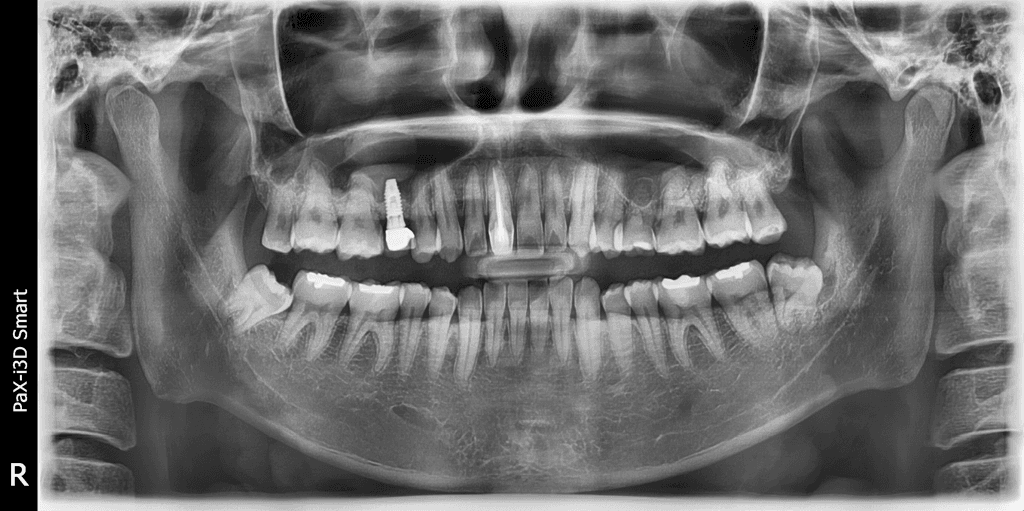

뼈 모양에 따라 임플란트가 튀어나와 보일 수 있으며 임플란트 했어도 교정치료는 가능합니다.

유치로 인한 임플란트는 영구치가 선천적으로 결손 상태라 유치를 최대한 오래 쓰다가 임플란트를 하는경우가 꽤 있습니다.

임플란트 치아가 있는 경우 치아의 움직임에 제한이 있기에 치아교정이 어려울수 있습니다.